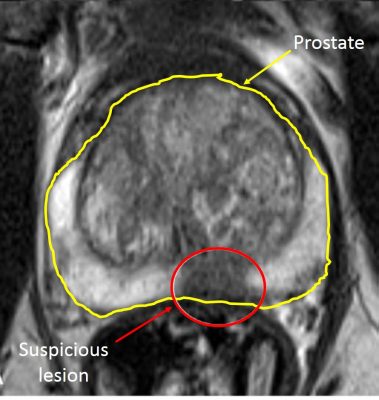

WHAT mpMRI SHOWS

MRI uses strong magnets and radio waves—not radiation—to create detailed images. A multiparametric study combines complementary sequences in one visit to reveal both anatomy and tissue behavior:

- T2-weighted imaging (anatomy): Clear detail of the gland, capsule, and zones.

- Diffusion-weighted imaging (DWI): How water moves through tissue (changes with cell density).

- Dynamic contrast–enhanced (DCE): Blood-flow patterns (used selectively).